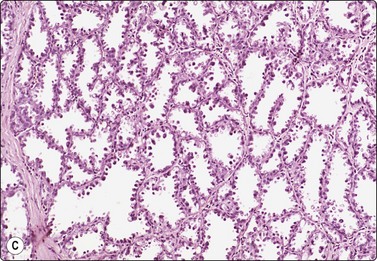

Breast tissue in pregnancy and lactation (Fig. 7.8)

image image image

Fig. 7.8 Lactating breast

Dispersed acinar cells with abundant pale and fragile cytoplasm, rounded nuclei and prominent central nucleoli; background of lipid secretions (A, MGG, HP; B, H & E, HP oil); (C) Corresponding tissue section (H&E, IP).

Criteria for diagnosis

Cellular smears,

Poorly cohesive, mainly dispersed epithelial cells of acinar type,

Cells have abundant fragile cytoplasm with secretory vacuoles and frayed borders,

Rounded vesicular nuclei and central nucleoli,

Dirty background due to lipid secretion and stripped nuclei with prominent nucleoli,

Single bipolar nuclei difficult to find.

FNB is very useful in reducing surgical intervention to a minimum during pregnancy and lactation. The pattern seen in FNB smears of ‘lumps’ in a pregnant or lactating breast can be problematic to inexperienced eyes and cause concern for malignancy.93,94 Smears are usually cellular. The cells are enlarged and arranged in loose groups or singly. The cells have an abundant fragile cytoplasm, vacuolated and finely granular. Nuclei are round, central, larger than the usual ductular cells, and have distinct small nucleoli (Fig. 7.8B). Some epithelial nuclei are stripped of cytoplasm. Single naked bipolar/oval nuclei are difficult to find. The background of abundant milky secretion with numerous lipid droplets seen as vacuoles is characteristic of actively secreting breast tissue and is the main clue to the diagnosis (Fig. 7.8A).